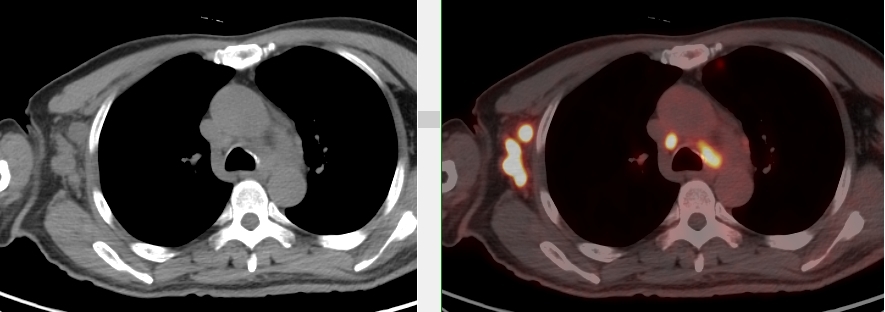

完善PET/CT檢查示:右側腋窩、雙側中下頸部、縱隔、雙側肺門多發(fā)MT,建議淋巴結活檢。后患者行右腋窩淋巴結切除活檢術,經北京大學第三醫(yī)院病理科會診示:右腋窩淋巴結惡性腫瘤,呈淋巴竇內生長模式,瘤細胞呈上皮樣,異型性明顯,伴中性粒細胞浸潤。結合病史及免疫組化,考慮為SMARCA4(BRG1)缺失的胸部腫瘤,伴神經內分泌標記表達。

本例為罕見病理類型的腫瘤,影像學表現無明顯特異性,診斷困難。強化CT和穿刺病理已基本明確為惡性腫瘤,行PET/CT檢查一是為了全身檢查,完善分期,二是根據PET代謝情況指導進行生物靶區(qū)活檢,進一步明確病理診斷。最終,PET/CT除縱隔病變外發(fā)現更多頸胸部淋巴結代謝異常,綜合考慮后對腋窩淋巴結進行切除活檢,最終得到病理證實。